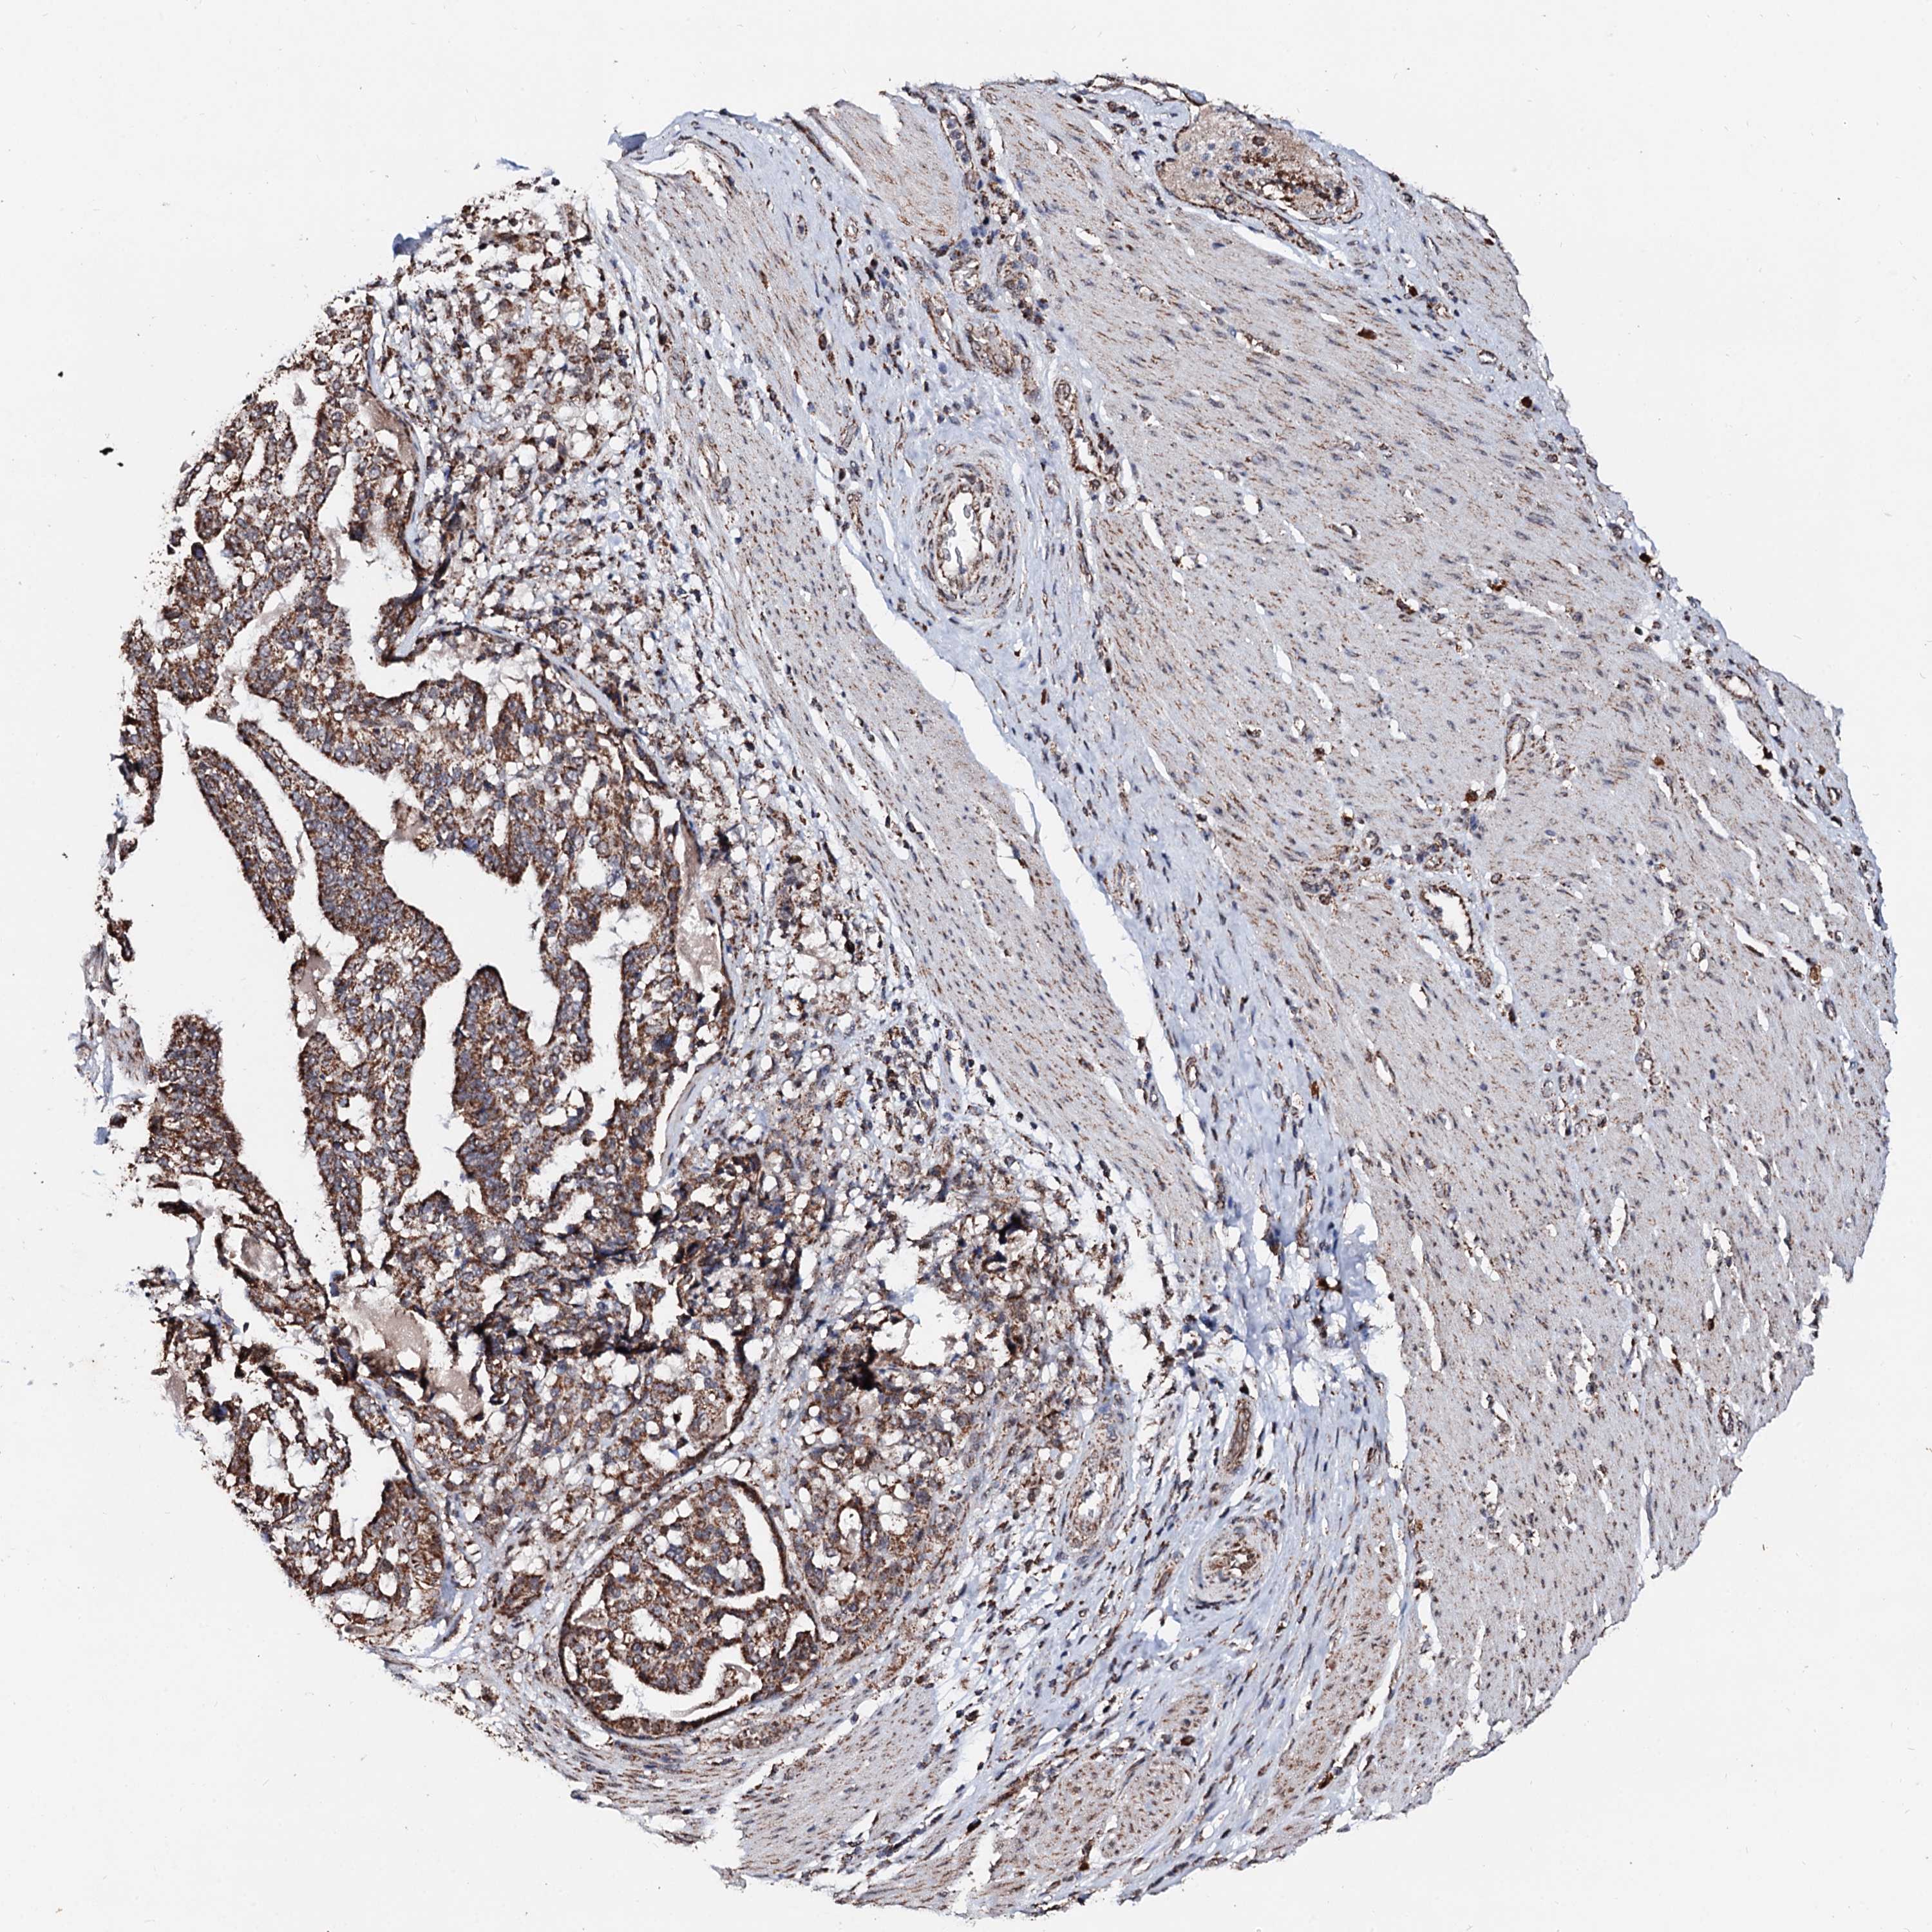

STOMACH CANCER - Protein expressioni

A mouse-over function shows sample information and annotation data. Click on an image to view it in a full screen mode. Samples can be filtered based on level of antibody staining by selecting one or several of the following categories: high, medium, low and not detected. The assay and annotation is described here.

Note that samples used for immunohistochemistry by the Human Protein Atlas do not correspond to samples in the TCGA dataset.

Antibody stainingi

Antibody staining in the annotated cell types in the current human tissue is reported as not detected, low, medium, or high, based on conventional immunohistochemistry profiling in selected tissues. This score is based on the combination of the staining intensity and fraction of stained cells.

Each image is clickable and will lead to virtual microscopy that enables deeper exploration of all samples and also displays staining intensity scores, fraction scores and subcellular localization as well as patient and tissue information for each sample.

Antibody HPA039875

Staining

High

Medium

Low

Not detected

Intensity

Strong

Moderate

Weak

Negative

Quantity

>75%

75%-25%

<25%

None

Location

Nuclear

Cytoplasmic/membranous

Cytoplasmic/membranous,nuclear

Adenocarcinoma, NOS